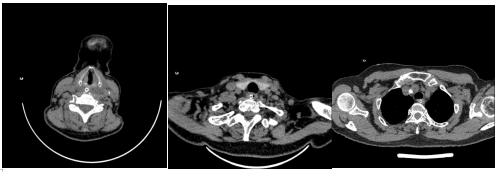

患者王女士(化名)因误吞枣核半天就诊于清华大学附属垂杨柳医院消化内科。完善颈胸部CT提示食管内异物,颈根部及纵隔内少许积气,考虑穿孔可能。病情危重,经联系胸外科副主任医师胡晓丹后讨论后决定先行内镜下异物取出,术后禁食水1周,予抗感染治疗。

颈胸部CT可见食管入口处异常密度灶,颈根部及纵隔内少许积气

术后患者于消化内科住院治疗,在主治医师谢俏、刘颖的细致诊治下,患者脱离险境,3天后复查颈胸部CT,颈根部及纵隔内少许积气完全吸收。

3天后复查颈胸部CT,颈根部及纵隔内少许积气完全吸收